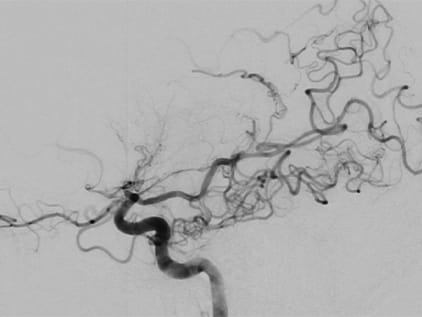

One study that is helpful in diagnosis of moyamoya disease is the cerebral angiogram. This is a test in which dye is injected into your brain to help doctors visualize the blood flowing to the brain. The images will show any blockage and also will allow the doctors to see the cluster of tiny blood vessels at the base of the brain that is the telltale sign of moyamoya disease.